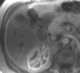

Avascular or hypovascular liver lesion

May Be Caused by